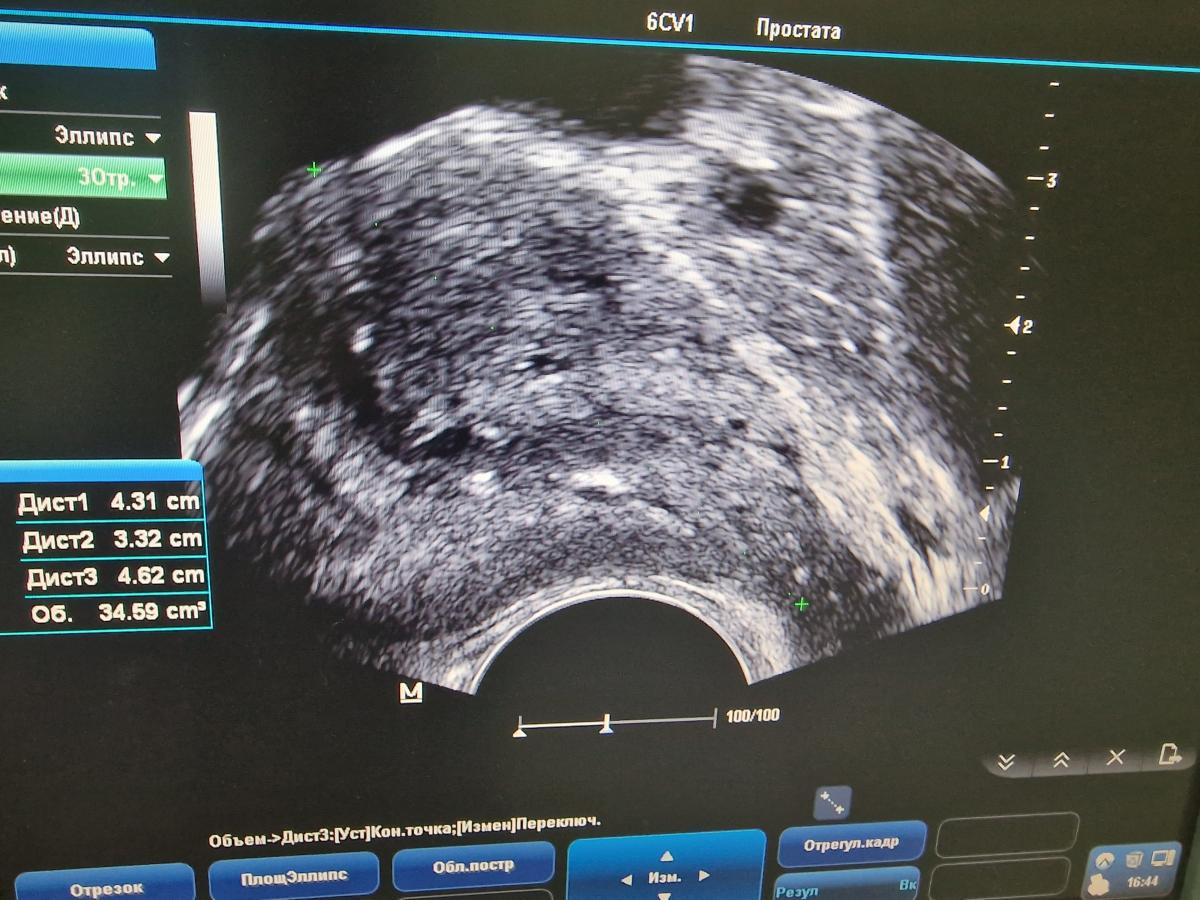

При пальпации или визуальном исследовании простаты отмечается ее увеличение или деформация.

- IV.УЗИ простаты и органов малого таза.